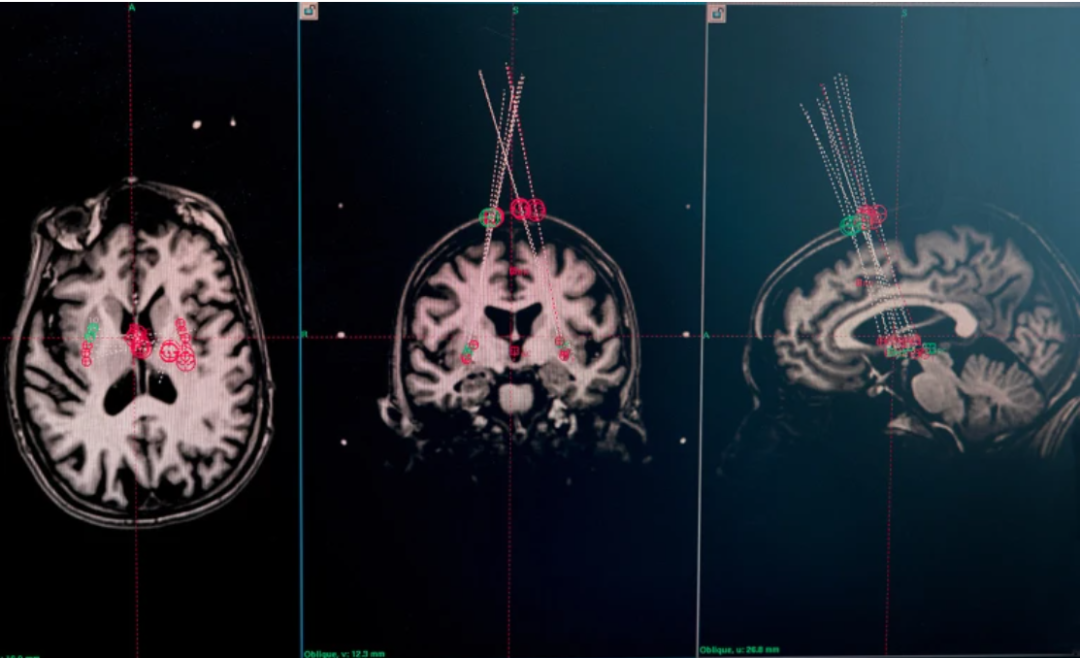

▲试验参与者的脑部 MRI 扫描用于计划针头将细胞输送到何处

bemdaneprocel(BRT-DA01):由人胚胎干细胞(hESC)分化成多巴胺前体细胞,植入帕金森患者双侧纹状体。在Ⅰ期(NCT04802733)中,患者在18个月随访内维持安全性良好,PET显像显示多巴胺摄取增加。

京都大学CiRA的iPSC方案:使用诱导多能干细胞来源的多巴胺前体,在jRCT2090220384试验中,高剂量组^{18}F-DOPA摄取↑45%,无肿瘤形成,功能评分改善显著。

两种技术路线各有优势:hESC细胞来源稳定,便于规模化;iPSC则来自患者自体细胞,免疫排斥风险较低。

更重要的是,这些移植不仅“存活”,还功能性产多巴胺,相当于在患者大脑中“重建工厂”。这为帕金森病的治疗带来可能的“疾病修正”,而不只是对症缓解。